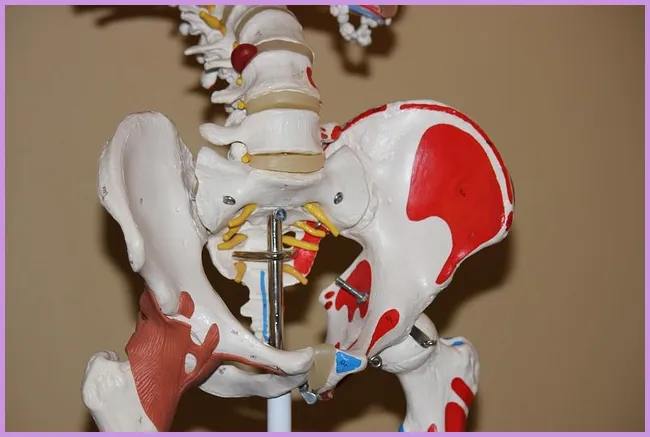

관절 통증의 원인에는 여러 가지가 있습니다. 가장 흔한 원인은 노화입니다. 나이가 들면서 관절의 연골이 마모되고 약해지기 때문입니다. 또한, 유전적인 요소나 자주 사용하는 부위의 과도한 사용도 원인이 될 수 있습니다. 각종 부상이나 외상의 영향도 무시할 수 없습니다.